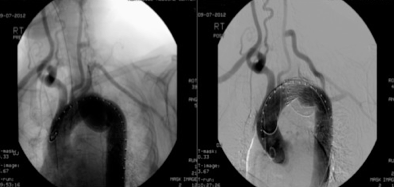

Blunt Traumatic laceration Of The Aorta - E-jacme.com

An aortic laceration with active bleeding was diagnosed (Fig. 2A and B). We immediately consulted with thoracic and cardiovascular surgeons to continue resuscitative measures and to arrange emergency surgery for the patient. However, within 30 ... Access Full Source